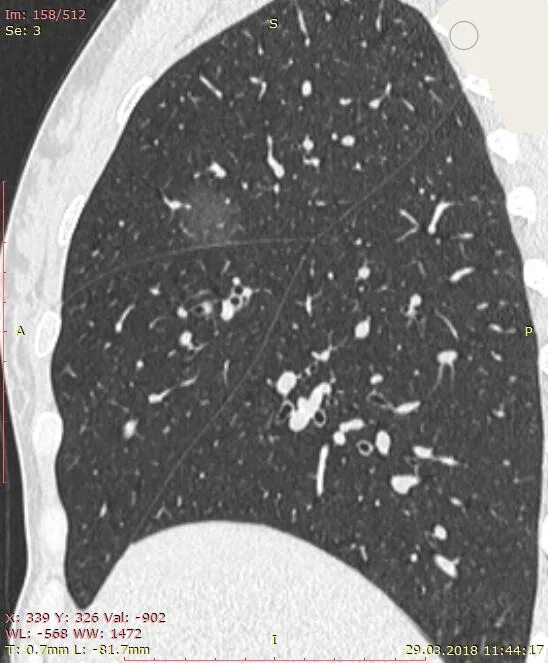

Уплотнения паренхимы по типу матового стекла